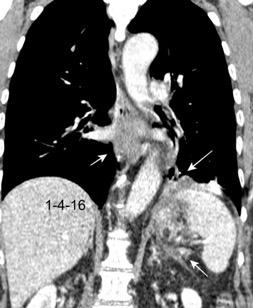

Colecciones “inflamatorias” abdominales llegan al tórax vía el hiato esofágico o por vía transdiafragmática

Afectación transdiafragmática: 5,6-43,7% de quistes hepáticos. “Área desnuda” del hígado.

Panda A et al. “Straddling Across Boundaries”. Thoracoabdominal Lesions: Spectrum and Pattern Approach. Curr Probl Diagn Radiol. 2015 Área desnuda. El hígado en contacto directo con el tendón central del diafragma. Contiene el hiato de VCI.